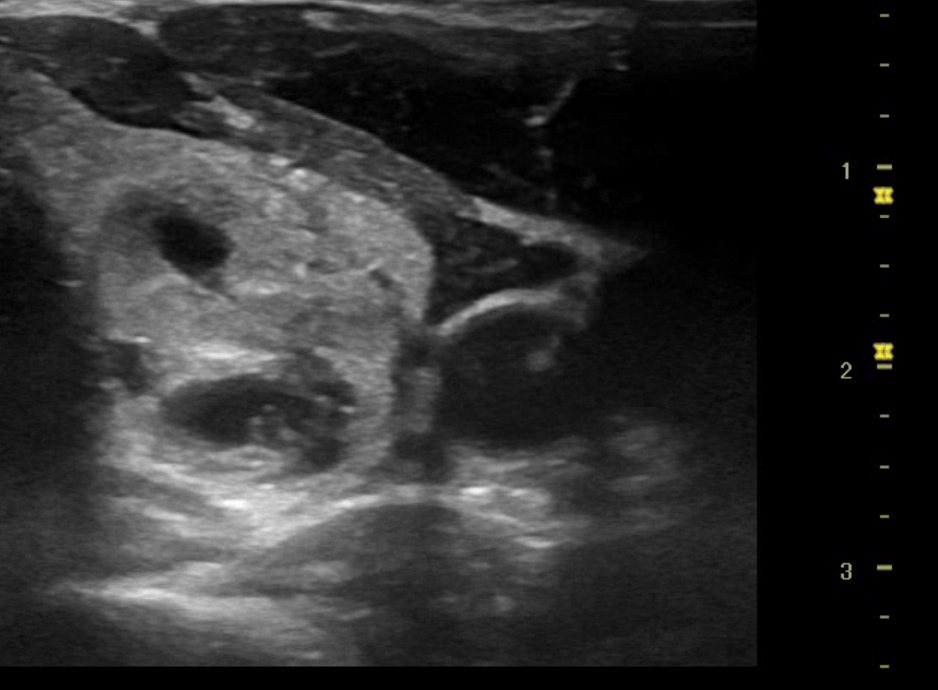

Se realizó ecografía en servicio de urgencias el cual encontramos los siguientes hallazgos:

Nódulo en polo inferior de lóbulo izquierdo de aproximadamente 2.08 X 1.47 x 3.63 cm de características de morfologías: con longitud mas alto que ancho, se observa trabéculas heterogéneas, visualizacion de leve vascularización sin evidencias de adenopatías colindantes, no se aprecia efecto masa en estructuras colindantes.